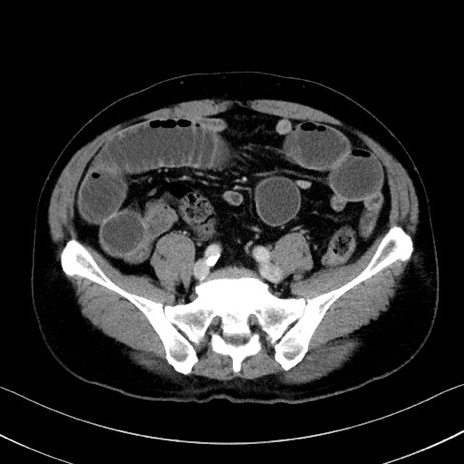

症例35(横断像)

【症例】70歳代 男性

【主訴】腹部膨満、嘔吐

【現病歴】昨日より腹部膨満感出現。本日増悪し、仙痛出現。嘔吐あり、受診。

【既往歴】糖尿病、胆摘後

【身体所見】BP 149/80mmHg、HR 74/min、BT 35.9℃、腹部:膨満、軟、圧痛なし。腸雑音減弱あり。上腹部正中切開瘢痕あり。

【データ】WBC 13500、CRP 1.72